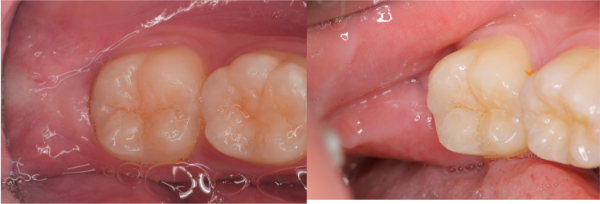

拔牙後傷修處理-卡食物-#38

口腔外科

拔牙後傷口處理